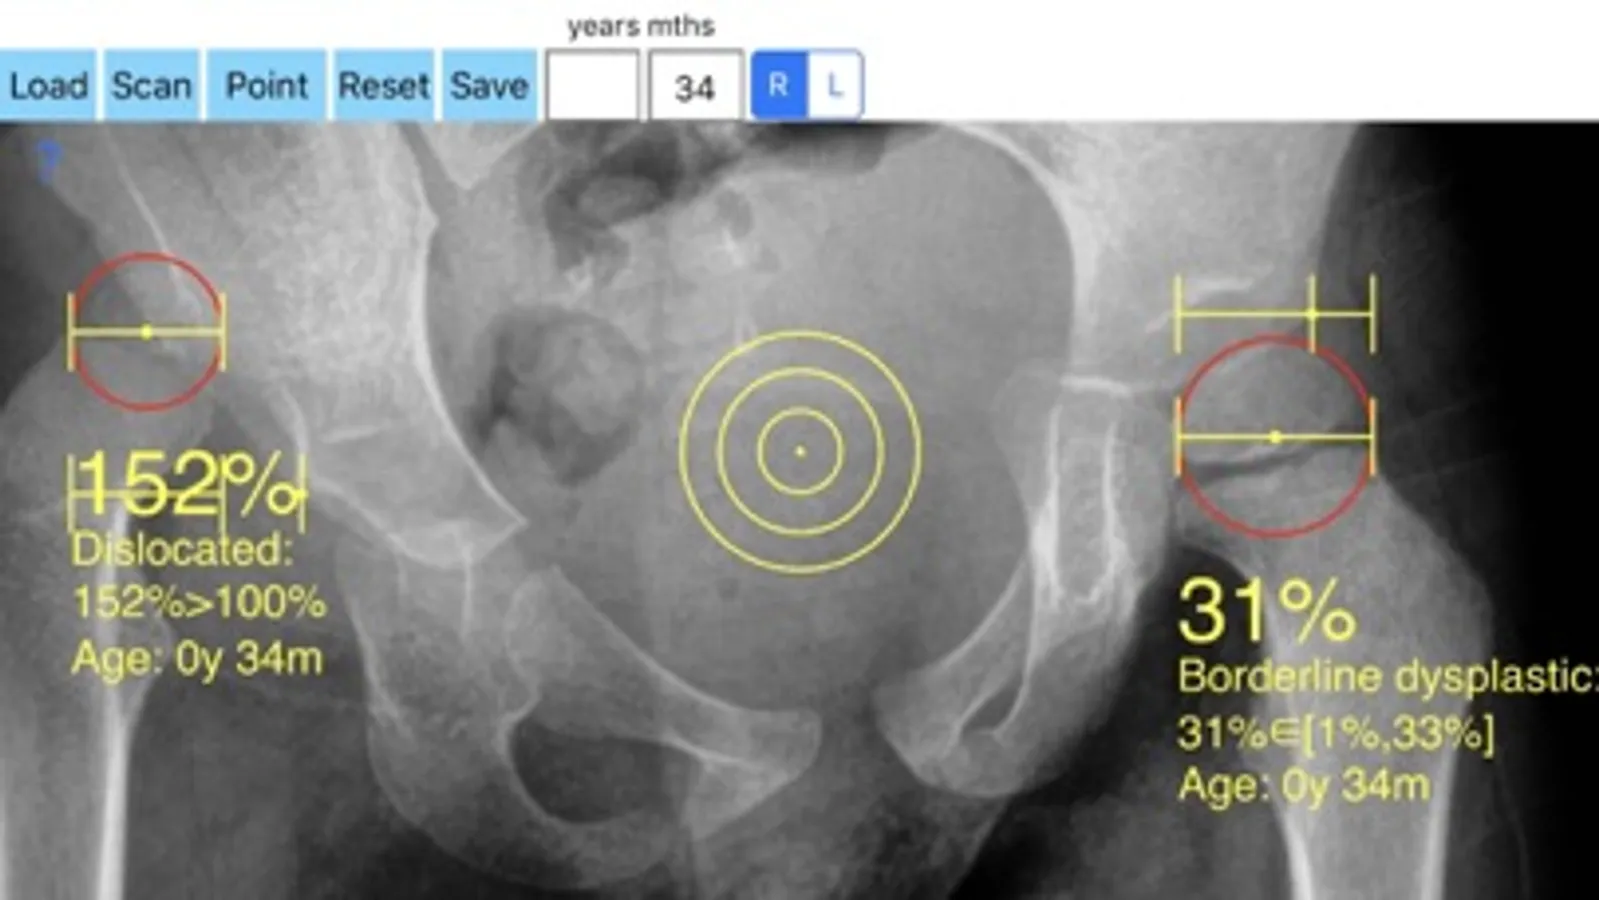

-Offers a very convenient way to determine the most accurate possibly way of measuring the percentage of femoral head which is not covered. By the aid of a circular transparent template which help to mark accurately the points of interest and the dynamic graphics who has been especially developed, by clicking only two points the percentage is calculated. By inputting the age of the patient in the App, the measured values in percentage are compared with values from normal reference database accordingly. In cases the percentage of uncovered femoral head of the hip is beyond the normal range for the relevant age, the hips are categorised as borderline dysplastic or dysplastic ready to subluxate or subluxated, dysplastic luxated or dislocated .